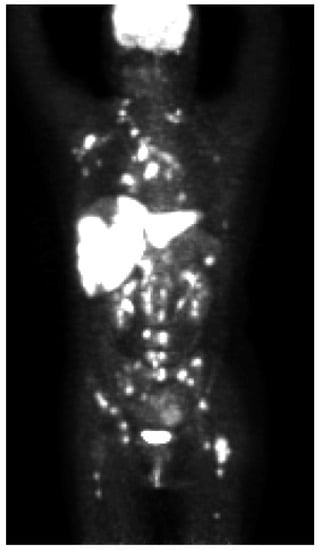

[18F]FDG PET/CT and PET/MR in Patients with Adrenal Lymphoma: A Systematic Review of Literature and a Collection of Cases

Aim. The present study aimed to assess the existing data about Primary Adrenal Lymphoma (PAL) evaluated with FDG PET and to describe a small monocentric series of cases. A systematic analysis (from 2010 to 2022) was made by using PubMed and Web of Science databases reporting data about the role of FDG PET/CT in patients with suspicious or known adrenal lymphoma. The quality of the papers was assessed by using QUADAS-2 criteria. Moreover, from a single institutional collection between 2010 and 2021, data from patients affected by adrenal lymphoma and undergoing contrast-enhanced compute tomography (ceCT)/magnetic resonance (MR) and FDG PET/CT or PET/MR were retrieved and singularly described. Seventy-eight papers were available from PubMed and 25 from Web of Science. Forty-seven (Nr. 47) Patients were studied, most of them in the initial staging of disease (n = 42; 90%). Only in one paper, the scan was made before and after therapy. The selected clinical cases were relative to the initial staging of disease, the restaging, and the evaluation of response to therapy. PET/CT and PET/MR always showed a high FDG uptake in the primary adrenal lesions and in metastatic sites. Moreover, PET metrics, such as maximum standardized uptake value (SUVmax) and metabolic tumor volume (MTV), were elevated in all primary adrenal lesions. In conclusions, FDG PET either coupled with CT or MRI can be useful in staging, restaging, and for the evaluation of treatment response in patients affected by PAL Full article

Figure 1